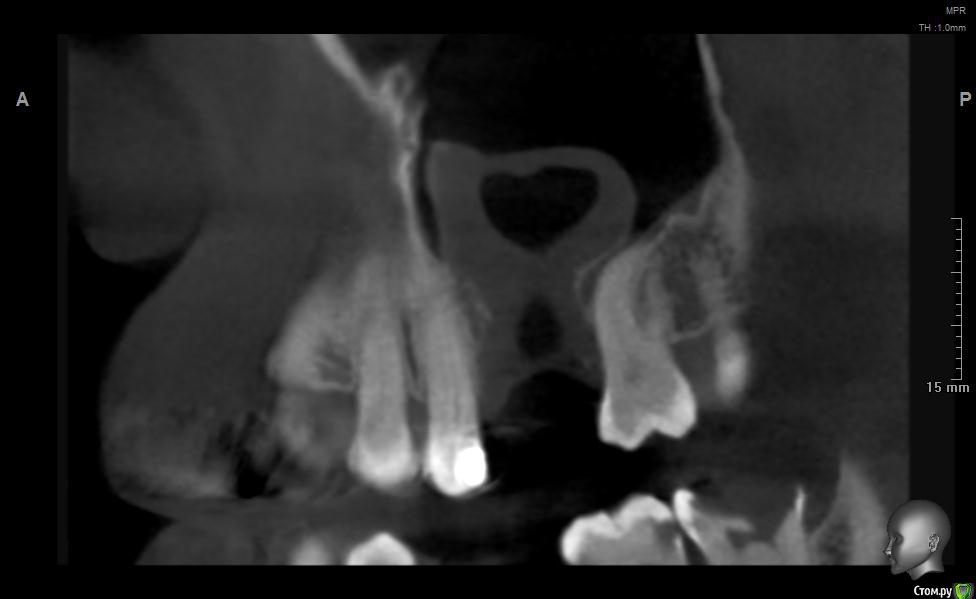

jm3300 Опубликовано 20 мая, 2019 Поделиться Опубликовано 20 мая, 2019 Добрый день. Пациент не мой, причины удаления, а так же о ходе удаления сказать ничего не могу. Известно лишь, что после удаления из лунки получили много зеленоватой жидкости. Удаляли с месяц назад. До сих пор имеется не сильно зияющая дырка. Нужно что то делать или просто ждать пока вторичным затянется. И если имплант планировать- ожидать ли там самостоятельного появления обьема кости? Ссылка на комментарий

L.E.S.I.K. Опубликовано 20 мая, 2019 Поделиться Опубликовано 20 мая, 2019 Я бы сделал ревизию через лунку, убрал оболочку кисты (похоже что она там осталась, или это эпителий врос - не важно) и провел бы закрытие небным лоскутом. При направлении в ЧЛХ есть вероятность, что наведут "разруху"(по Колддвел-Люк) и пациент получит проблему при дальнейшей реабилитации. З.Ы. На данных срезах не видно остиомеатальный комплекс- крайне желательно, чтобы он был не блокирован. 3 Ссылка на комментарий

Дмитрий М Опубликовано 21 мая, 2019 Поделиться Опубликовано 21 мая, 2019 месяц прошел, уже ничего не дождетесь, кость там не вырастет т.к. уже пошла эпителизация. так и останется не сильно зияющая дырка только вы видите клиническую картину, поэтому вам решать какой вариант лучше выбрать.в любом случае удалять кисту, оболочку, вероятно будет сообщение, которое необходимо закрывать и по ситуации готовиться к обоим вариантам по снимкам это скорее киста, (прослеживается кортикальная по контуру) 1 Ссылка на комментарий

Дмитрий Л. Опубликовано 21 мая, 2019 Поделиться Опубликовано 21 мая, 2019 Там уже есть сообщение с гайморовой. Возможно не функционирующее. Вяло текущий хронический воспалительный процесс. Ждать мало смысла. Если стремиться сделать всё как можно менее инвазивно, можно пойти по такому пути:1. Недельку попромывать соустье антисептиками. Воспаление стихнет. Десны добавится.2. Расскрыться. Аспирировать слизистую слюноотсосом. Кюретаж, всё через лунку. Если функционирующего соустья не было, оно появится.3. Небный лоскут, чтоб ушить соусье. Сосудосуживающие в нос, антибиотики. Ссылка на комментарий

jm3300 Опубликовано 21 мая, 2019 Автор Поделиться Опубликовано 21 мая, 2019 Ну по КТ и клинически сообщения с пазухой нет. Пациента,кроме наличия самой лунки, вообще ничего не беспокоит. Ссылка на комментарий